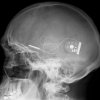

The device is implanted in the patient’s head and is powered via a separate battery pack that is wireless and located outside of the body. Underneath the retina, a grid containing 1500 electrodes is implanted, a method said to provide the patient with a higher resolution sight than other options.The implant works by detecting light.

The amount of light detected can be controlled by the patient via a dial that is located behind the ear. The grid works in much the same way as the light-detecting cells in the eyes, and for this reason it does not work for just any type of blindness. Rather, it works for those who have lost their vision due to a condition that has destroyed the eye’s ability to detect light.